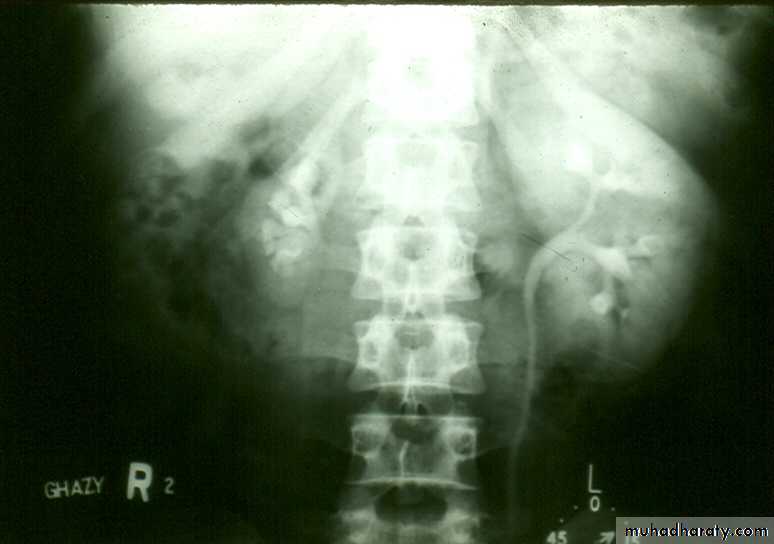

IVU shows :

The kidneys at low position .

Close to the spine with long axis parallel to the spine .

Mal–rotation manifested by medially directed calyces.

The renal pelvis and ureters are anterior and lateral in position .

Fusion of upper poles is rare.

HORSE –SHOE KIDNEY

HORSE SHOE KIDNEY